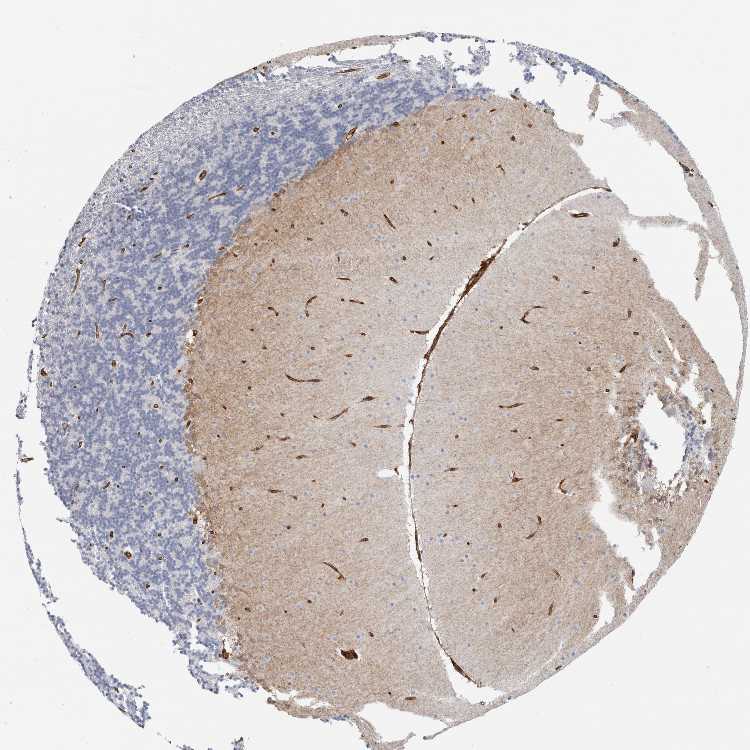

CEREBELLUM - Antibody stainingi

Antibody staining in the annotated cell types in the current human tissue is reported as not detected, low, medium, or high, based on conventional immunohistochemistry profiling in selected tissues. This score is based on the combination of the staining intensity and fraction of stained cells.

Each image is clickable and will lead to virtual microscopy that enables deeper exploration of all samples and also displays staining intensity scores, fraction scores and subcellular localization as well as patient and tissue information for each sample.

Antibody HPA019010Antibody HPA019070Antibody HPA026643

Purkinje cells MediumLowNot detected

Cells in granular layer Not detectedNot detectedNot detected

Cells in molecular layer MediumLowLow